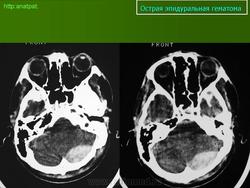

1. КТ головного мозга пациента с двухсторонними эпидуральными гематомами.